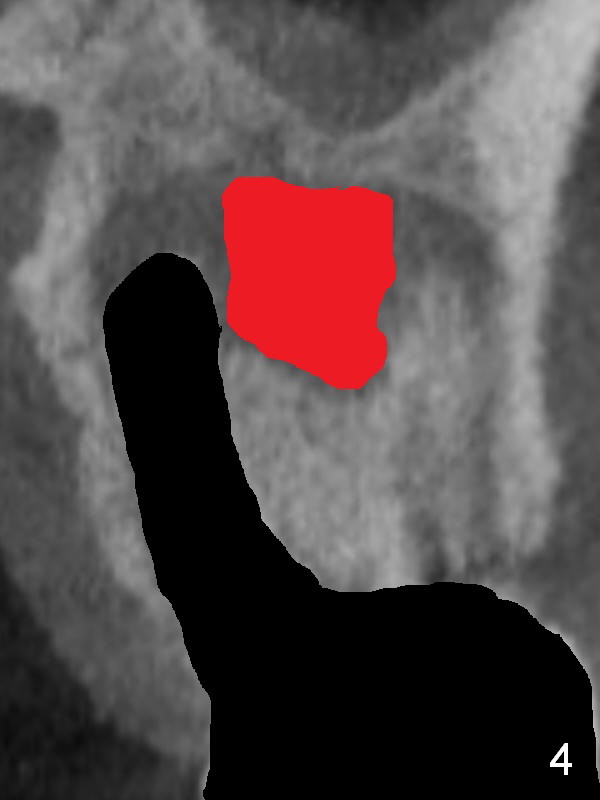

There is purulent discharge from the mesiobuccal fistula (Fig.1 <) during the tooth #14 extraction. Fig.2 is a coronal section of CBCT of the affected tooth showing a large apical lesion (*). When the tooth is removed (Fig.3), limited amount of granulation tissue is removed apical to the palatal root (P in Fig.2). The granulation tissue (Fig.4 red area) above the septum (Fig.3 S) is thoroughly extirpated when the septum is removed (Fig.5 black area).